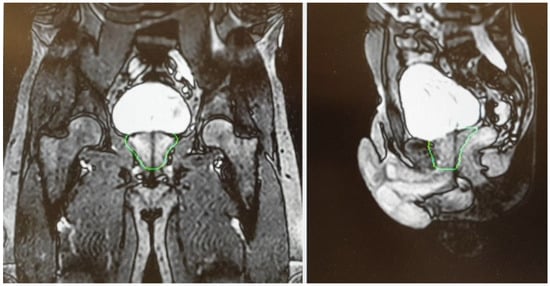

- Cuccia, F.; Mazzola, R.; Nicosia, L.; Giaj-Levra, N.; Figlia, V.; Ricchetti, F.; Rigo, M.; Vitale, C.; Corradini, S.; Alongi, F. Prostate reirradiation: Current concerns and future perspectives. Expert Rev. Anticancer Ther. 2020, 20, 947–956. [Google Scholar] [CrossRef]

- Cuccia, F.; Nicosia, L.; Mazzola, R.; Figlia, V.; Giaj-Levra, N.; Ricchetti, F.; Rigo, M.; Vitale, C.; Corradini, S.; Ruggieri, R.; et al. Linac-based SBRT as a feasible salvage option for local recurrences in previously irradiated prostate cancer. Strahlenther. Onkol. 2020, 196, 628–636. [Google Scholar] [CrossRef]

- Pasquier, D.; Martinage, G.; Janoray, G.; Rojas, D.P.; Zerini, D.; Goupy, F.; De Crevoisier, R.; Bogart, E.; Calais, G.; Toledano, A.; et al. Salvage Stereotactic Body Radiation Therapy for Local Prostate Cancer Recurrence After Radiation Therapy: A Retrospective Multicenter Study of the GETUG. Int. J. Radiat. Oncol. 2019, 105, 727–734. [Google Scholar] [CrossRef] [PubMed]

- Jereczek-Fossa, B.A.; Rojas, D.P.; Zerini, D.; Fodor, C.; Viola, A.; Fanetti, G.; Volpe, S.; Luraschi, R.; Bazani, A.; Rondi, E.; et al. Reirradiation for isolated local recurrence of prostate cancer: Mono-institutional series of 64 patients treated with salvage stereotactic body radiotherapy (SBRT). Br. J. Radiol. 2019, 92, 20180494. [Google Scholar] [CrossRef]